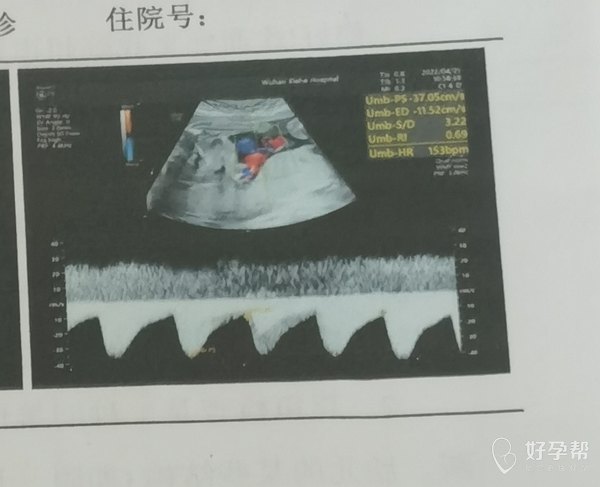

这个图是心脏吗下面的是心脏波动吗我看别人的上

这个应该测的是脐带的血流,主要是看收缩期,舒张期血流频谱,计算S/D值。咱们重点应该关注的是S/D值,再结合孕周考虑,孕39周正常小于3。